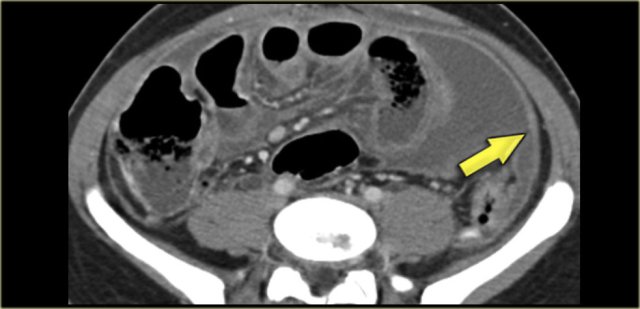

Sclerosing Mesenteritis

This disease has multiple synonyms reflecting the wide histologic spectrum: mesenteric panniculitis, fibrosing mesenteritis and mesenteric lipodystrophy.

Pathologically it is a chronic inflammation of unknown etiology.

This entity is more common than previously thought.

The signs and symptoms are variable.

Patients present with pain, a palpable mass or bowel complications, but in many cases it is an incidental finding on CT made for other reasons.

The image on the left is the form that we most frequently see in patients that are screened for other reasons.

This form is mostly named panniculitis mesenterialis.

In a more advanced stage you can have significant fibrosis resulting in retraction of the small bowel.

Within these masses dystrophic calcifications can be seen as well as lucent areas of fat (arrow)